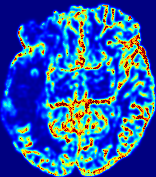

LesionRefer to captionRefer to captionRefer to captionRefer to captionRefer to captionRefer to caption𝐕rgbsubscript𝐕𝑟𝑔𝑏{\bf{V}}_{rgb}Refer to captionRefer to captionRefer to captionRefer to captionRefer to captionRefer to caption𝐕2subscriptnorm𝐕2{\|\bf{V}}\|_{2}Refer to captionRefer to captionRefer to captionRefer to captionRefer to captionRefer to captionRefer to caption3.53.53.52.82.82.82.12.12.11.41.41.40.70.70.70.00.00.0(mm/s)𝑚𝑚𝑠(mm/s)D𝐷DRefer to captionRefer to captionRefer to captionRefer to captionRefer to captionRefer to captionRefer to caption0.0200.0200.0200.0160.0160.0160.0120.0120.0120.0080.0080.0080.0040.0040.0040.0000.0000.000(mm2/s)𝑚superscript𝑚2𝑠(mm^{2}/s)Slice #1Slice #2Slice #3Slice #4Slice #5Slice #6

Figure 3: PIANO feature maps for one stroke patient, where the lesion is located in the left hemisphere. Top row: segmented stroke lesion region (white) on different slices, obtained from ISLES 2017. The corresponding slices for the PIANO feature maps are shown in the following rows.

For a better insight into an estimated velocity field 𝐕𝐕{\bf{V}} and diffusion field 𝐃𝐃{\bf{D}}, we compute the following maps: (1) 𝐕rgbsubscript𝐕𝑟𝑔𝑏{\bf{V}}_{rgb}: Color-coded orientation map of 𝐕=(Vx,Vy,Vz)T𝐕superscriptsuperscript𝑉𝑥superscript𝑉𝑦superscript𝑉𝑧𝑇{\bf{V}}=(V^{x},V^{y},V^{z})^{T}, obtained by normalizing 𝐕𝐕{\bf{V}} to unit length and mapping its 3 components to red, green, blue respectively; (2) 𝐕2subscriptnorm𝐕2\|{\bf{V}}\|_{2}: 222 norm of 𝐕𝐕{\bf{V}}; (3) D𝐷D: scalar field in Eq. 5.

Fig. 3 and Fig. 4 show the PIANO feature maps estimated from two ISLES 2017 patients: all are highly consistent with the lesion in both cases. Details of the blood flow trajectories are revealed in 𝐕rgbsubscript𝐕𝑟𝑔𝑏{\bf{V}}_{rgb} by the ridged patterns and the sharp changes of colors in the unaffected (right) hemisphere, while the flat patterns appearing within the lesion provide little directional information about the velocity and indicate low velocity magnitudes. Velocity magnitudes are more directly visualized via 𝐕2subscriptnorm𝐕2\|{\bf{V}}\|_{2}, from which one can easily locate the lesion where 𝐕2subscriptnorm𝐕2\|{\bf{V}}\|_{2} is low. D𝐷D also indicates lower diffusion values in the lesion, though with less contrast potentially due to the fact that it captures the accumulated effect of CA diffusion at the voxel-level.